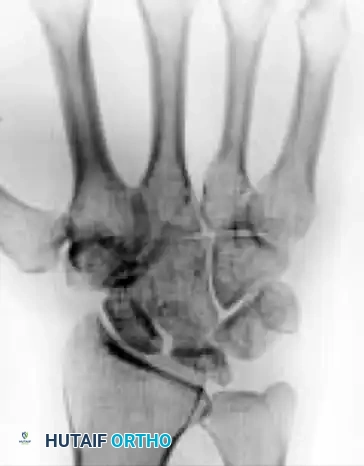

Armistead et al., utilizing CT imaging, demonstrated that occult fractures of the lunate are present in a significant subset of Kienböck patients.

A common fracture pattern is the anterior pole type, which isolates the anterior pole from the remaining bone. The compressive force exerted by the capitate distracts the fracture, diminishing the likelihood of healing. As the dorsal portion of the lunate collapses, the anterior pole may be extruded volarly. Furthermore, the ratio of carpal height to the length of the third metacarpal is reduced (normal is 0.54 ± 0.03), indicating overall carpal collapse.